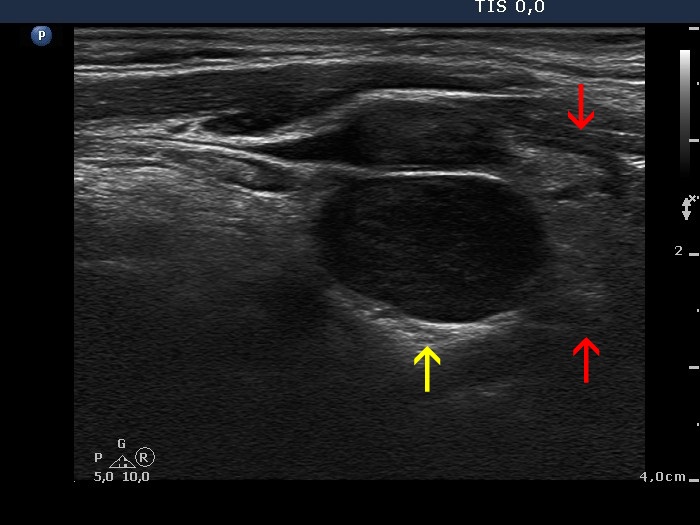

The echogenicity of the nodule - case 671 (ultrasonographic picture 4b)

Upper part of the left lobe, longitudinal scan. The hypoechogenic lesion marked with yellow arrow is located upper to the thyroid which is pointed with red arrows.